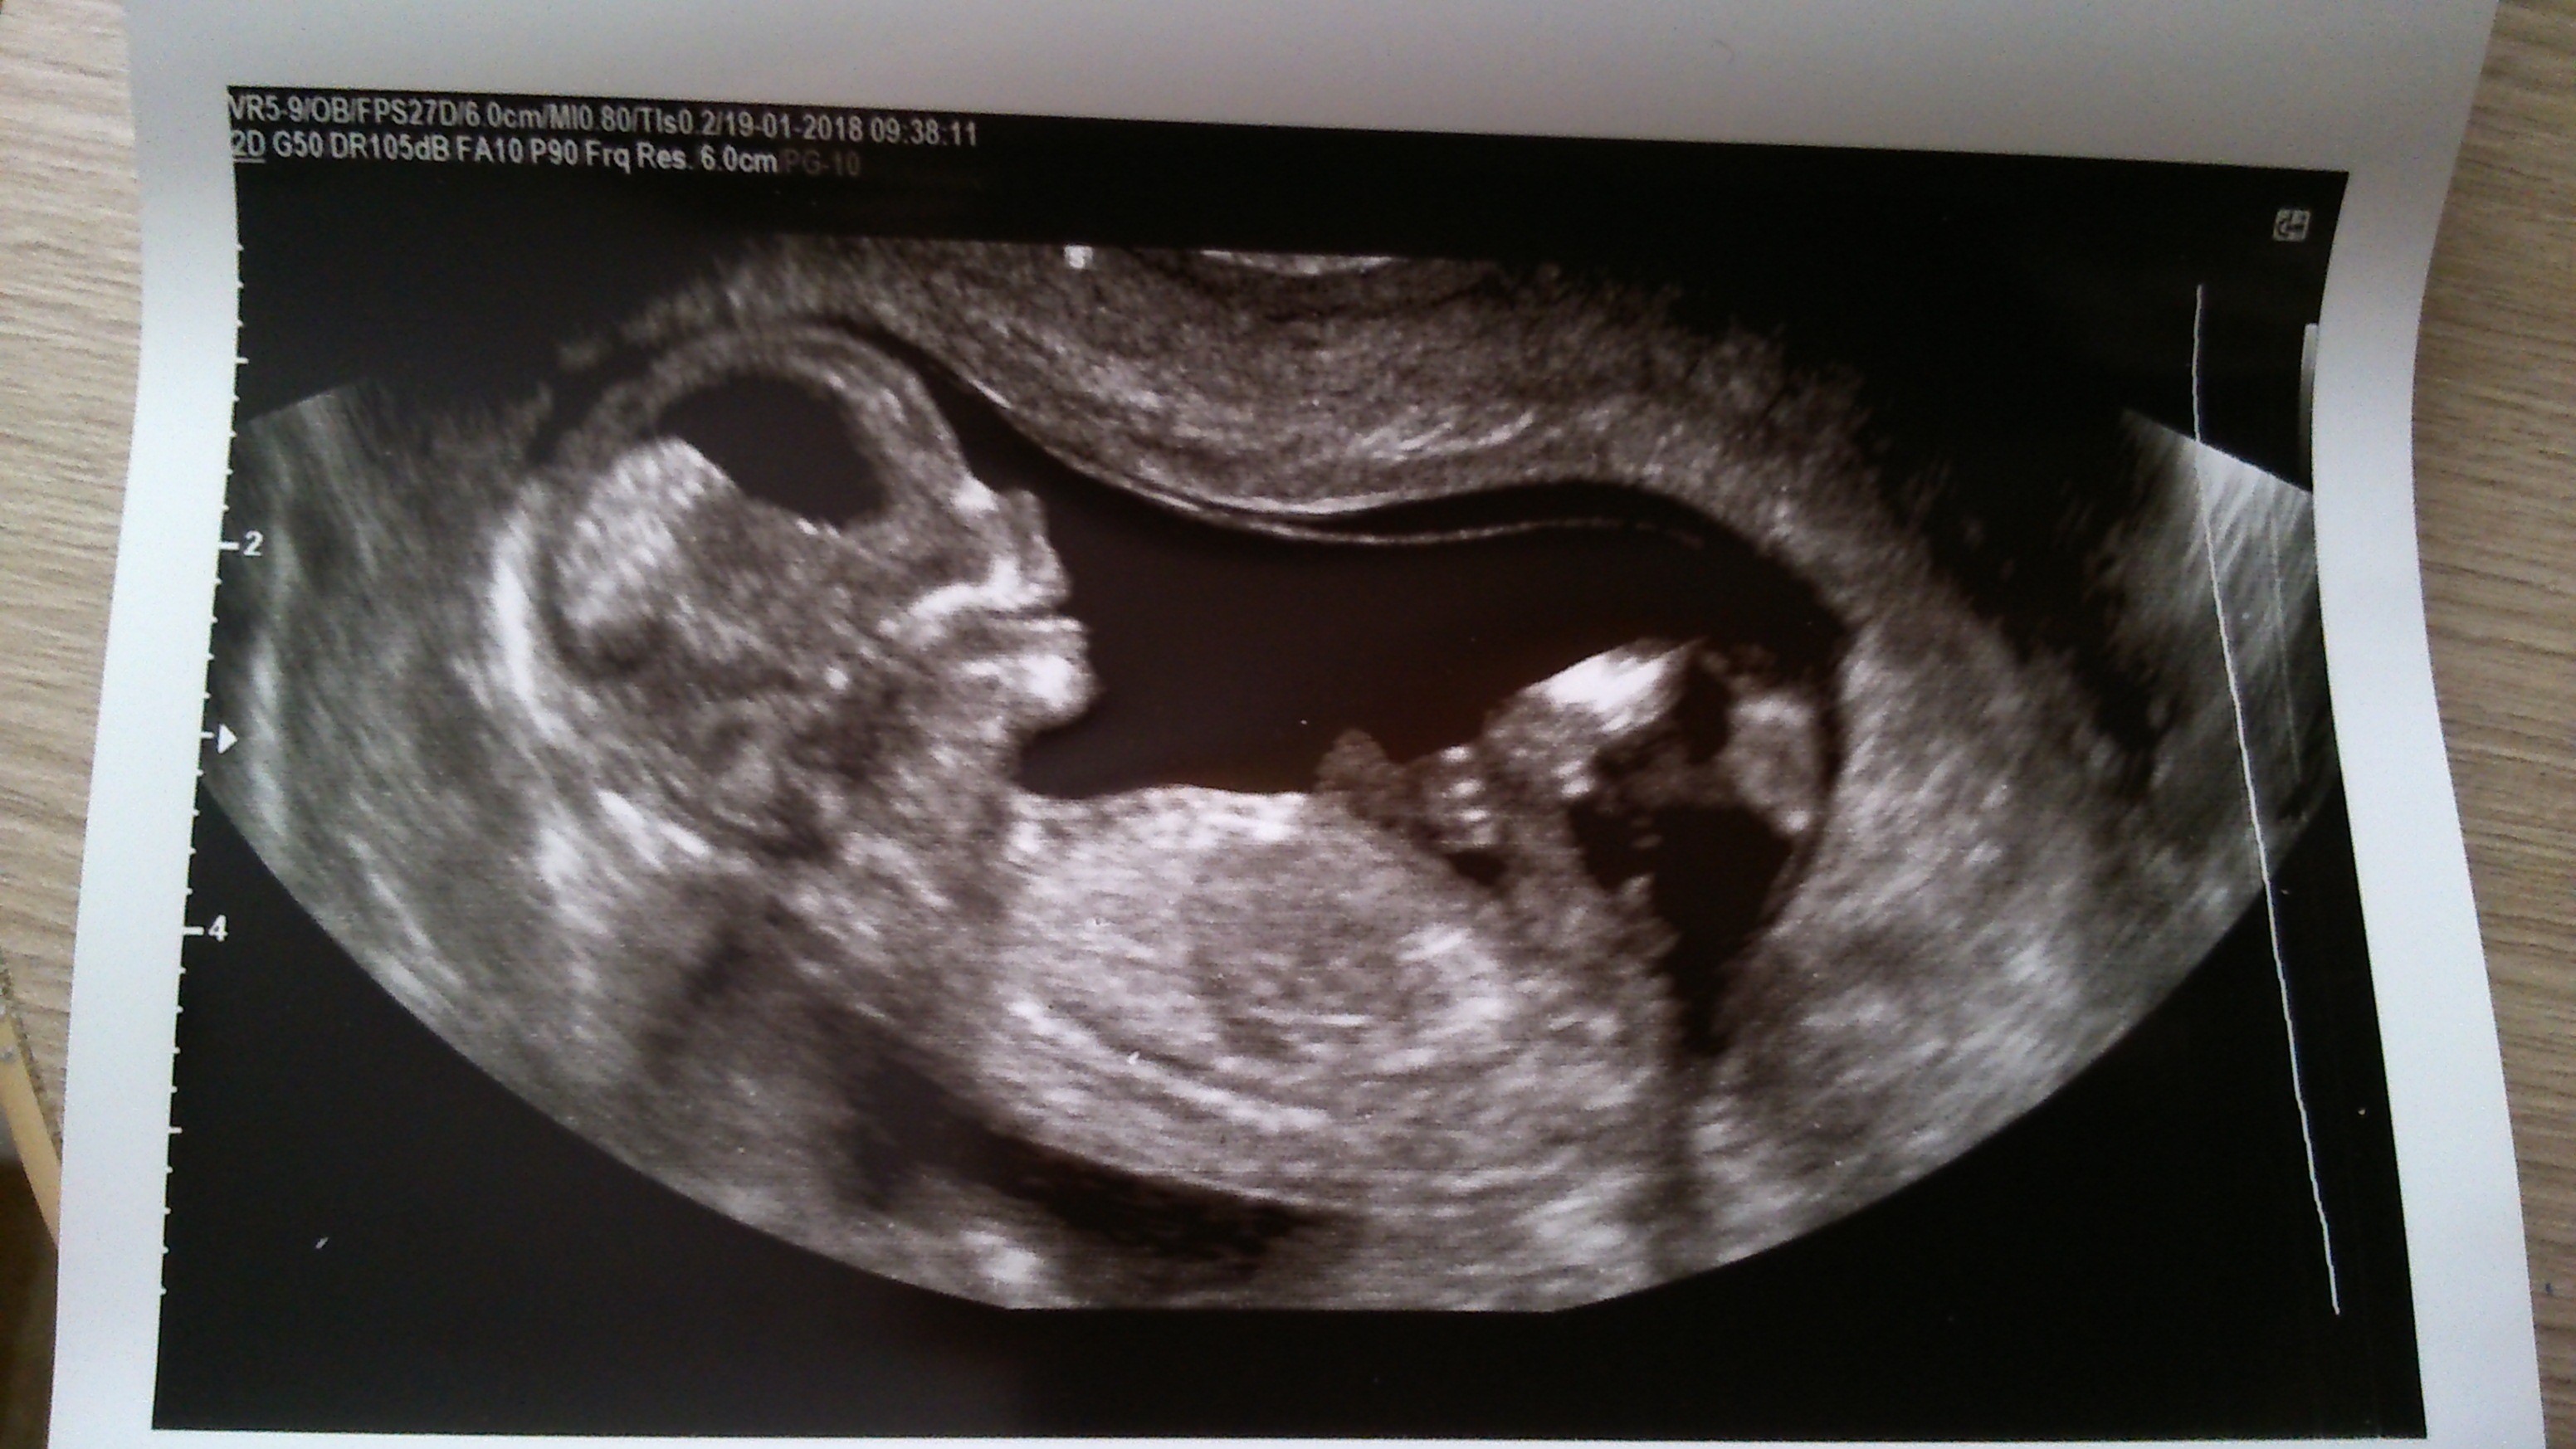

Piosior i jajcynta [emoji1] [emoji1]Czy tylko mi się wydaje że pod nóżkami jest siusior stoi?czy to pepowia Zobacz załącznik 835996

trzeba czekać, ja do polowkowego a Ty? ;-)Czy tylko mi się wydaje że pod nóżkami jest siusior stoi?czy to pepowia Zobacz załącznik 835996

Ja tam widzę siusioraCzy tylko mi się wydaje że pod nóżkami jest siusior stoi?czy to pepowia Zobacz załącznik 835996

A lekarz nic Ci nie powiedział czy coś tam widzi?mnie powiedział, że na tym etapie płeć okresla się na podstawie jakiegoś pęcherzyka czy wyrostka czy nie wiem jak to się nazywa

jak jest do góry to chłop a jak w poziomie to babeczka

jak tu wytrzymać w ciąży żyję się od wizyty do wizytyNiee.. Wszyscy widzą chyba siusioraJa tam widzę siusiora